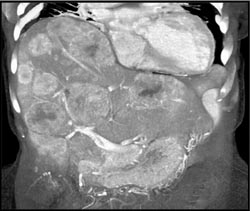

Diagnosis

Hemangioma